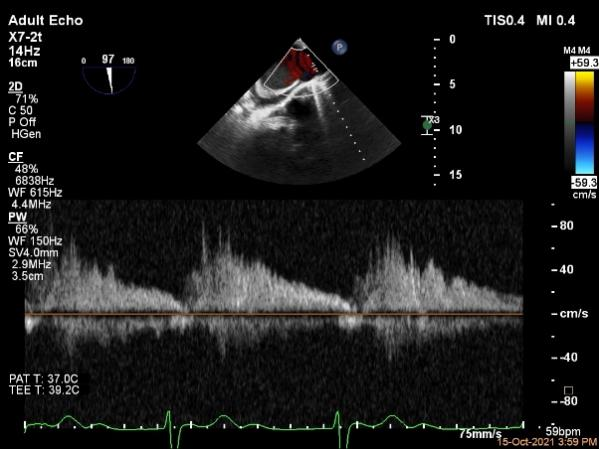

肺静脉血流频谱恢复正向